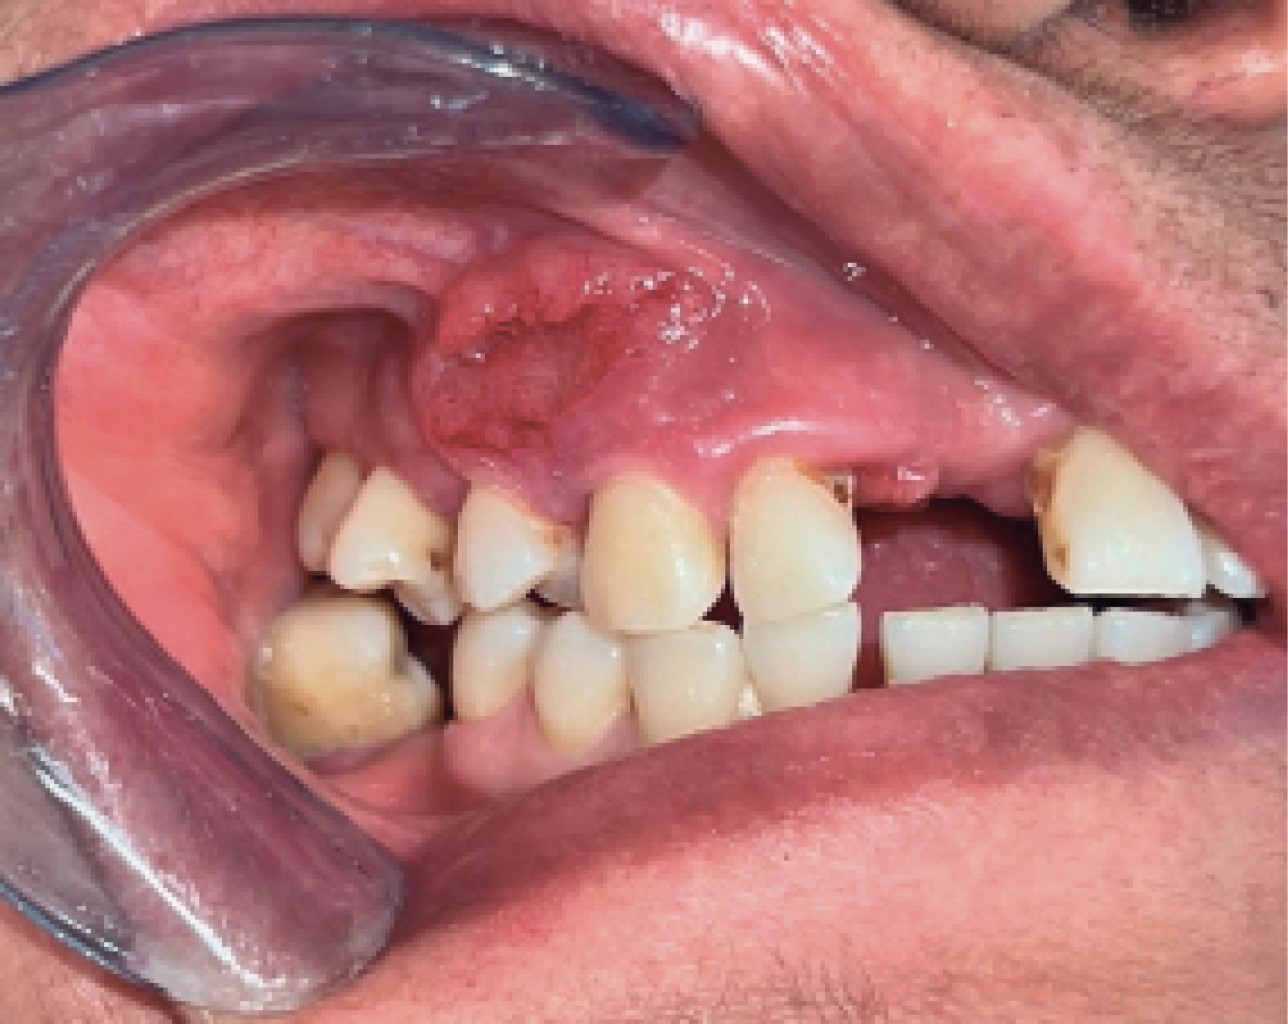

Figure 2